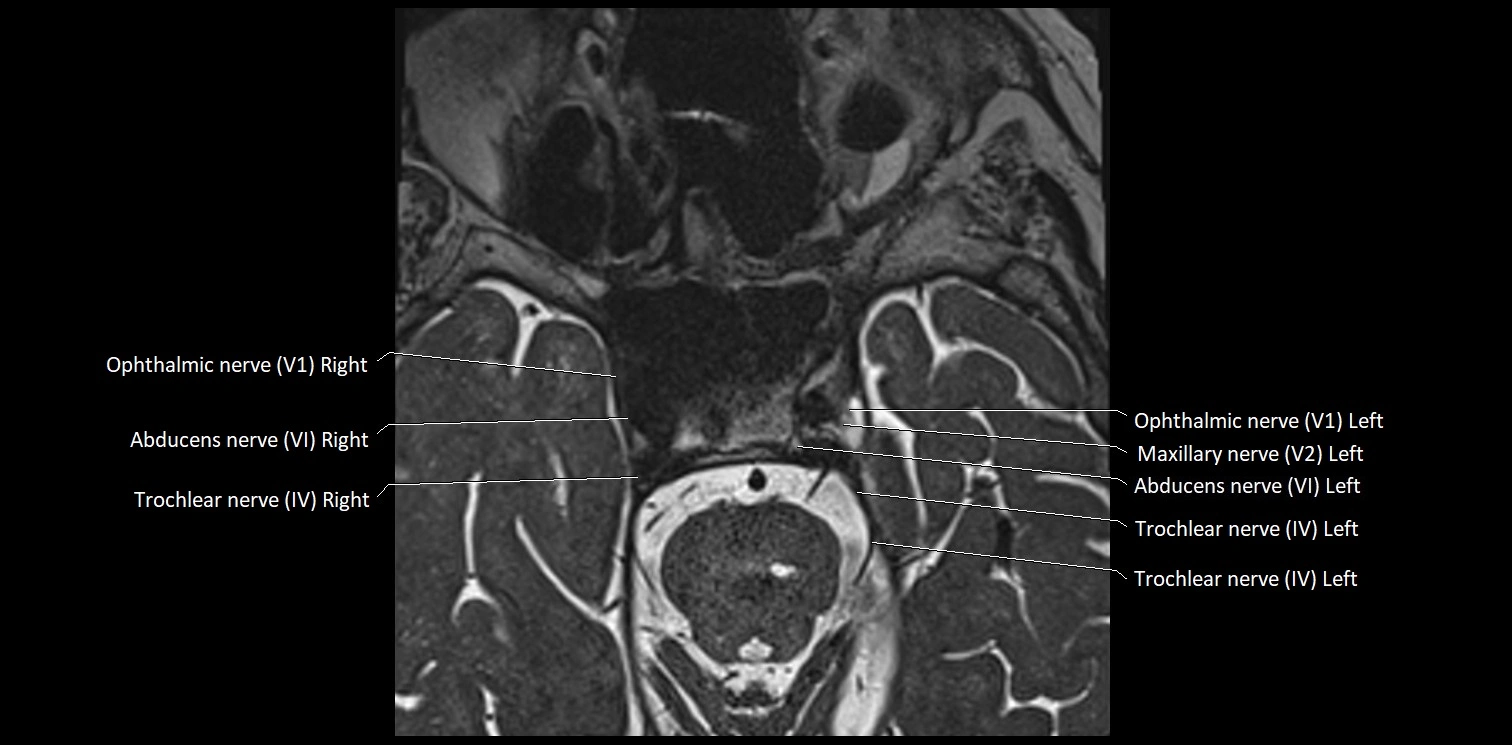

MRI Appearance

• The abducens nerve is a small, thin, linear structure

• Best visualized on high-resolution T2-weighted 3D MRI sequences (e.g., FIESTA or CISS)

• Seen as a hypointense (dark) line running from the brainstem at the pontomedullary junction, traversing the prepontine cistern, and entering Dorello’s canal under the petrosphenoidal ligament, then into the cavernous sinus, and finally the orbit

• May be challenging to visualize in standard MRI due to its small size

• Pathology may be inferred by absence, displacement, or enhancement of the nerve

MRI images

image